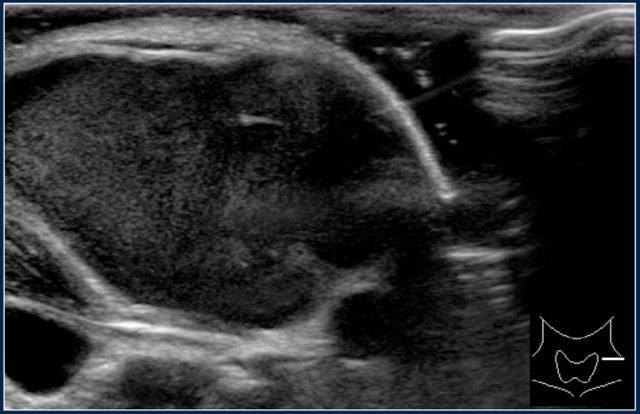

Hình ảnh của một bé trai mười bốn tuổi với khối sưng không đau ở cổ bên trái.

Siêu âm cho thấy nhiều hạch bạch huyết giảm âm phóng to, không có rốn hạch tăng âm.